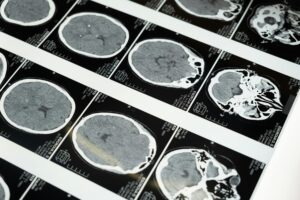

Un derrame cerebral puede rejuvenecer el cerebro

Después de un derrame cerebral, el cerebro puede hacer algo sorprendentemente esperanzador: puede «refrescar» partes ...